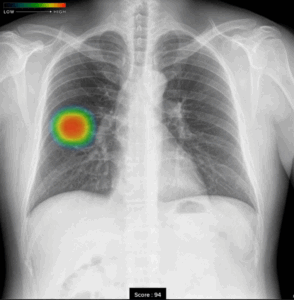

*胸部レントゲン検査・・・・・2,800円(税込み)

肺がん・結核・肺炎等の有無を調べます。心臓肥大や大動脈の状態も知ることができます。

当院では病変の見逃しを減らすために最新のAI器機(Fuji film EX-Mobile) を導入し、AIによる診断を併用しています。